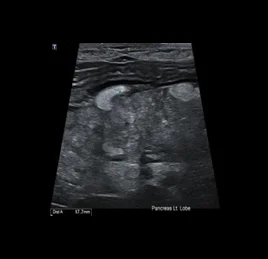

• 췌장염

• 췌장 농양